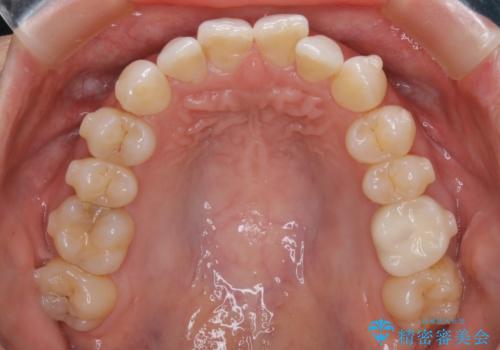

【抜歯】矯正治療とインプラントで正常な噛み合わせを実現

- 元々は矯正治療を主訴にご来院されました。

治療を始めるにあたり、精密検査を受けていただき全体の状況を把握したうえで矯正治療の計画を立てることとなりました。

その過程で左下の6番目の歯は治療が必要な状態であることが分かり、被せ物を外して内部を確認してみると根が破折してしまっていることが判明しました。

歯が深い位置で破折している場合は基本的には抜歯が選択されます。

様々な治療プランを患者さんと相談させて頂き、最終的にインプラントで噛み合わせを回復させていくこととなり、まず悪くなっている歯を抜歯することから開始しました。